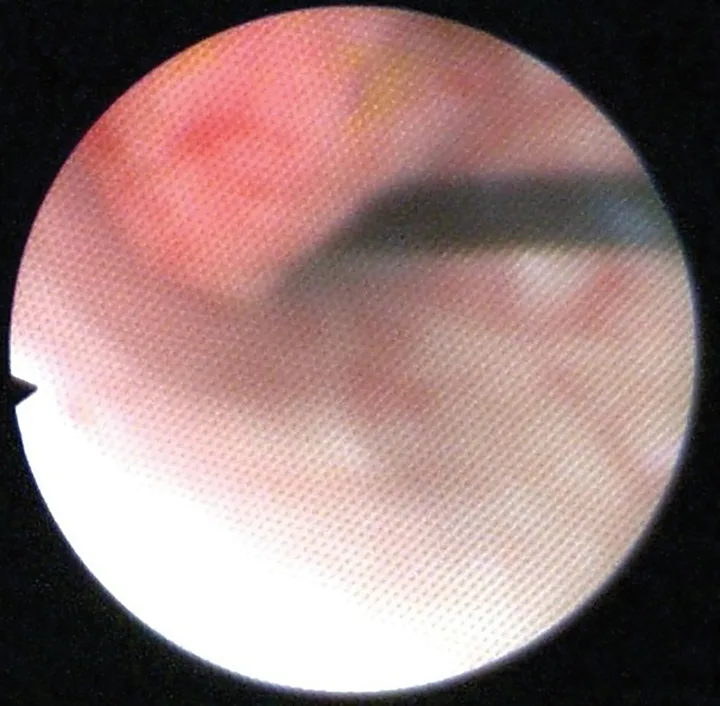

Abdominal ultrasound showed a mildly thickened cranioventral urinary bladder wall with a 6-mm irregular, polypoid, inhomogeneous mass extending into the lumen (Figure 1). No other abnormalities were identified in the abdomen. Cystoscopy revealed an irregular mass on the cranioventral wall with an area of ulceration and a fibrous tag protruding into the lumen (Figure 2). The remainder of the bladder appeared friable. Aerobic and Mycoplasma spp cultures of the bladder wall were negative. Histopathologic examination of biopsies showed mild lymphocytic cystitis.

FIGURE 1

Ultrasound image of a 6-mm polypoid mass extending into the lumen from the cranioventral bladder wall